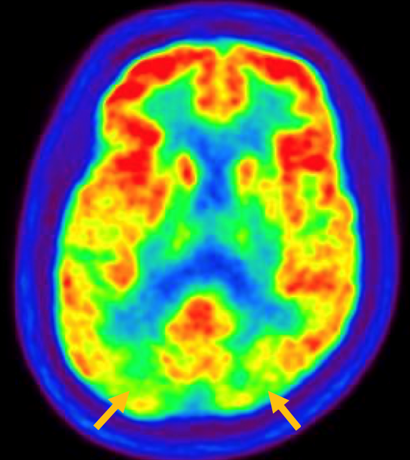

진행 핵상 마비는 대표적인 파킨슨 증후군 중의 하나입니다. 파킨슨병과 다른 점은 질병의 초기부터 중심을 잡기 어려운 체위 불안정이 나타나 자주 넘어진다는 것입니다. 파킨슨병의 경우 질병이 상당히 진행된 뒤에 체위 불안정이 나타납니다. 또한 진행 핵상 마비에서는 목 주위 근육을 비롯한 몸 중심 근육의 경축이 나타나, 목을 뒤로 젖히면서 걷는 모습이 보입니다. 그리고 눈의 운동을 조절하는 기능에 장애가 나타나 아래쪽을 바라보는 데 문제가 생겨 계단을 내려갈 때 어려움을 겪는 경우가 많습니다. 진행 핵상 마비가 의심되는 경우, 뇌 자기공명영상(MRI)에서 중뇌의 위축이 비정상적으로 심하게 나타나는 소견을 확인하거나, 뇌포도당 양전자 단층촬영(PET)에서 전두엽과 중뇌의 대사 기능이 저하된 소견을 확인하여 진단에 참고할 수 있습니다.

[진행핵상마비 환자의 뇌포도당 양전자 단층 촬영에서 확인되는 중뇌의 대사 저하 소견]